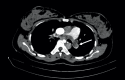

Figure 1.. CT-scan findings of chest